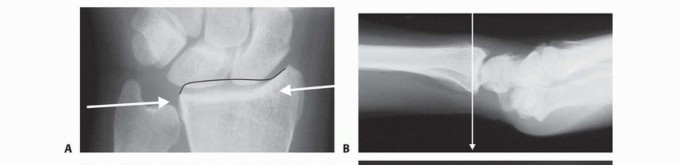

### FIG 4 • A. Positioning for standard lateral radiography. B. Standard lateral radiograph. C. Positioning for 10-degree lateral radiography. D. Ten-degree lateral radiograph. Note the improved visualization of the articular surface of the base of the scaphoid facet and the entire lunate facet. Injuries from a high-energy mechanism present as complex comminuted fractures of the articular surface with extension into the radial/ulnar shaft ( FIG 3I). ## IMAGING AND OTHER DIAGNOSTIC STUDIES Posteroanterior (PA), standard lateral ( FIG 4A,B), and 10-degree lateral views are routine views for radiographic evaluation of the distal radius. The 10-degree lateral view (FIG 4C,D) clearly visualizes the ulnar two-thirds of the articular surface from the base of the scaphoid facet through the entire lunate facet. Oblique views may also be helpful for evaluating the injury. The radiographic features of distal radius fractures include the following 8: Carpal facet horizon ( FIG 5A,B). This is the radiodense horizontal landmark that is used to identify the volar and dorsal rim on the PA view. If the articular surface has palmar tilt, the x-ray beam is tangential to the subchondral bone of the volar portion of the lunate facet, with the result that the carpal facet horizon identifies the volar rim. However, if the articular surface has displaced into dorsal tilt, the x-ray beam becomes tangential to the subchondral bone of the dorsal portion of the lunate facet instead, and the carpal facet horizon identifies the dorsal rim (not shown). The carpal facet horizon corresponds to the portion of the articular surface visualized on the 10-degree lateral x-ray projection. Teardrop angle (normal 70 ± 5 degrees; FIG 5C,D). The teardrop angle is used to identify dorsiflexion of the volar 79 rim of the lunate facet. Depression of the teardrop angle to a value less than 45 degrees indicates that the volar rim of the lunate facet has rotated dorsally and impacted into the metaphyseal cavity (axial instability pattern of the volar rim). This may be associated with axial and dorsal subluxation of the carpus. Restoration of the teardrop angle is necessary to correct this type of malreduction.

### FIG 5 • A. Carpal facet horizon (arrows). Used to differentiate between the volar and dorsal rim on the PA projection. B. Origin of carpal facet horizon. The carpal facet horizon is formed by that part of the articular surface that is parallel to the x-ray beam and depends on whether the articular surface is in volar or dorsal tilt. C. Normal teardrop angle. D. Depressed teardrop angle in this case is caused by axial instability of the volar rim. E. Normal articular congruency. F. Abnormal articular congruency, indicating disruption across the volar and dorsal surfaces of the lunate facet. G. AP interval is the point-to-point distance between the corners of the dorsal and volar rim. H. DRUJ interval. I. Normal lateral carpal alignment. J. Dorsal subluxation of the carpus. Congruency of the articular surface ( FIG 5E,F). The subchondral outline of the articular surface of the distal radius is normally both congruent and concentric with the subchondral outline of the base of the lunate; a uniform joint interval should be present between the radius and lunate along the entire articular surface. When the joint interval between these articular surfaces is not uniform, discontinuity and disruption of the lunate facet has occurred. Anteroposterior (AP) distance (normal: females 18 ± 1 mm, males 20 ± 1 mm; FIG 5G). The AP distance is the point-to-point distance from the dorsal to palmar rim of the lunate facet. It is best evaluated on the 10- degree lateral view. Widening of the AP distance implies discontinuity of the volar and dorsal portion of the lunate facet. 80 DRUJ interval ( FIG 5H). The DRUJ interval measures the degree of apposition between the head of the ulna and the sigmoid notch (normal: 2 mm or less). This parameter is best measured with the forearm in neutral rotation. Significant widening of the DRUJ interval implies disruption of the DRUJ capsule and TFCC. Coronal malalignment of the distal radial fragment is often suggested by widening of the DRUJ interval. Lateral carpal alignment ( FIG 5I,J). On the 10-degree lateral view and with the wrist in neutral position, the rotational center of the capitate normally aligns with a line extended from the volar surface of the radial shaft. Dorsal rotation of the volar rim results in a dorsal shift of lateral carpal alignment as the carpus subluxes dorsally. This may place the flexor tendons at a mechanical disadvantage, affecting grip strength. In addition to injury films, reassessing radiographs after reduction can be very helpful in determining the personality and specific components of a particular fracture. Computed tomography (CT) scans allow higher resolution and definition of fracture characteristics, particularly for highly comminuted fractures. Preferably, an attempt at closed reduction before obtaining a CT scan will help limit distortion of the image. CT scans are particularly helpful for visualizing intra-articular fragments as well as DRUJ disruption and incongruity of the sigmoid notch. Clinical evaluation of the carpus, interosseous membrane, and elbow, combined with radiographic studies when needed, should be included to identify the presence of other injuries that may affect the decision for a particular treatment. ## SURGICAL MANAGEMENT